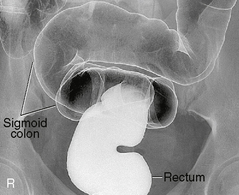

Alternative ventral decubitus projection is often performed for double-contrast studies.

Both right and left lateral decubitus are commonly taken as part of a double-contrast series.